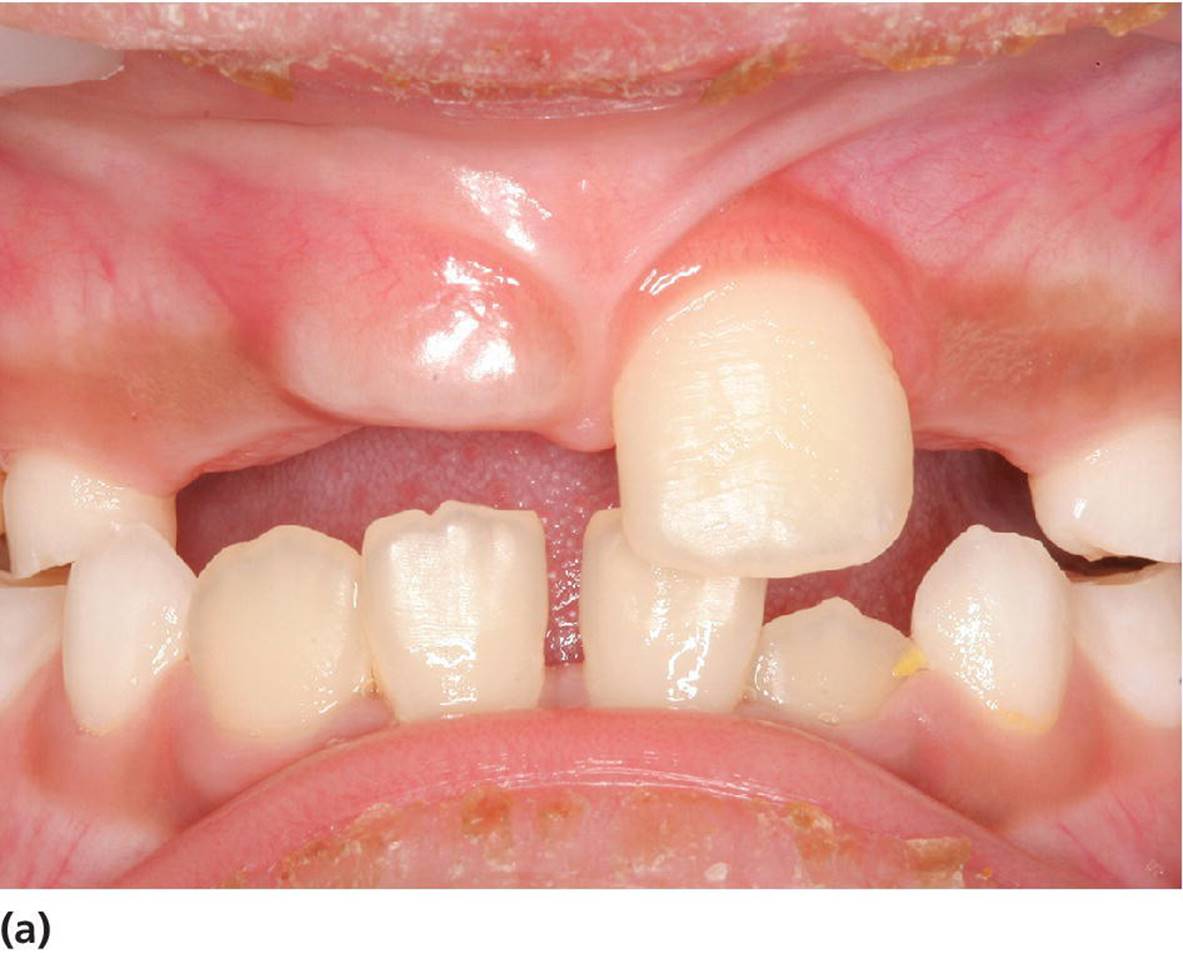

Denudation of impacted or nonerupting teeth

Figure 15.28 (a) Delayed eruption of upper central incisor. (b) Denudation of gingival mucosa to enchance eruption.